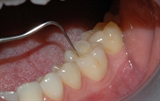

undersøkelse hos tannlegen

Tunge og slimhinner kontrolleres for å konstatere at alt er normalt.